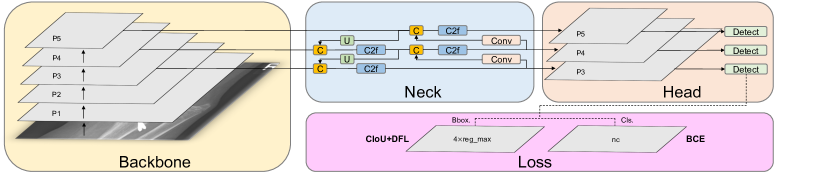

In this section, we introduce the process of the model training, validation and testing on the dataset, the architecture of YOLOv8 model, and the data augmentation technique employed during training. Figure 1 illustrates the flowchart depicting the model training process and performance evaluation. We randomly divide the 20,327 X-ray images of the GRAZPEDWRI-DX dataset into the training, validation, and test set, where the training set is expanded to 28,408 X-ray images by data augmentation from the original 14,204 X-ray images. We design our model according to YOLOv8 algorithm, and the architecture of YOLOv8 algorithm is shown in Figure 2.

Our model architecture consists of backbone, neck, and head, as shown in Figure 4. In the following subsections, we introduce the design concepts of each part of the model architecture, and the modules of different parts.

Backbone

The backbone of the model uses Cross Stage Partial (CSP) [61] architecture to split the feature map into two parts. The first part uses convolution operations, and the second part is concatenated with the output of the previous part. The CSP architecture improves the learning ability of the CNNs and reduces the computational cost of the model.

YOLOv8 [36] introduces C2f module by combining the C3 module and the concept of ELAN from YOLOv7 [32], which allows the model to obtain richer gradient flow information. The C3 module consists of 3 ConvModule and n DarknetBottleNeck, and the C2f module consists of 2 ConvModule and n DarknetBottleNeck connected through Split and Concat, as illustrated in Figure 4, where the ConvModule consists of Conv-BN-SiLU, and n is the number of the bottleneck. Unlike YOLOv5 [53], we use the C2f module instead of the C3 module.

Furthermore, we reduce the number of blocks in each stage compared to YOLOv5 to further reduce the computational cost. Specifically, our model reduces the number of blocks to 3,6,6,3 in Stage 1 to Stage 4, respectively. Additionally, we adopt the Spatial Pyramid Pooling - Fast (SPPF) module in Stage 4, which is an improvement from Spatial Pyramid Pooling (SPP) [62] to improve the inference speed of the model. These modifications lead to our model with a better learning ability and shorter inference time.

Neck

Generally, deeper networks obtain more feature information, resulting in better dense prediction. However, excessively deep networks reduce the location information of the object, and too many convolution operations will lead to information loss for small objects. Therefore, it is necessary to use Feature Pyramid Network (FPN) [48] and Path Aggregation Network (PAN) [63] architectures for multi-scale feature fusion. As illustrated in Figure 4, the Neck part of our model architecture uses multi-scale feature fusion to combine features from different layers of the network. The upper layers acquire more information due to the additional network layers, whereas the lower layers preserve location information due to fewer convolution layers.

Inspired by YOLOv5, where FPN upsamples from top to bottom to increase the amount of feature information in the bottom feature map; and PAN downsamples from bottom to top to obtain more the top feature map information. These two feature outputs are merged to ensure precise predictions for images of various sizes. We adopt FP-PAN (Feature Pyramid-Path Aggregation Network) in our model, and delete convolution operations in upsampling to reduce the computational cost.

Head

Different from YOLOv5 model utilizing a coupled head, we use a decoupled head [33], where the classification and detection heads are separated. Figure 4 illustrates that our model deletes the objectness branch and only retains the classification and regression branches. Anchor-Base employes a large number of anchors in the image to determine the four offsets of the regression object from the anchors. It adjusts the precise object location using the corresponding anchors and offsets. In contrast, we adopt Anchor-Free [64], which identifies the center of the object and estimates the distance between the center and the bounding box.

Loss